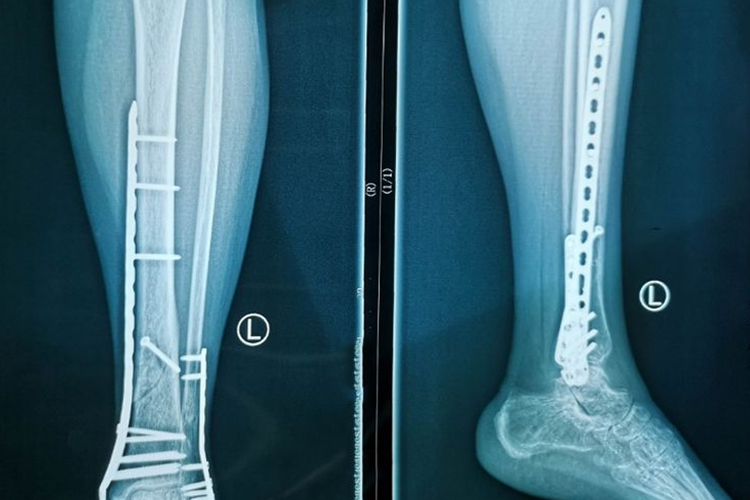

- 对于右胫腓骨下端的骨折,通常采用保守治疗(如石膏固定)或手术治疗(如钢板内固定)来确保骨折断端的稳定。在骨折愈合的初期,患者需要保持患肢的制动,以减少骨折部位的移动,促进骨痂的形成。